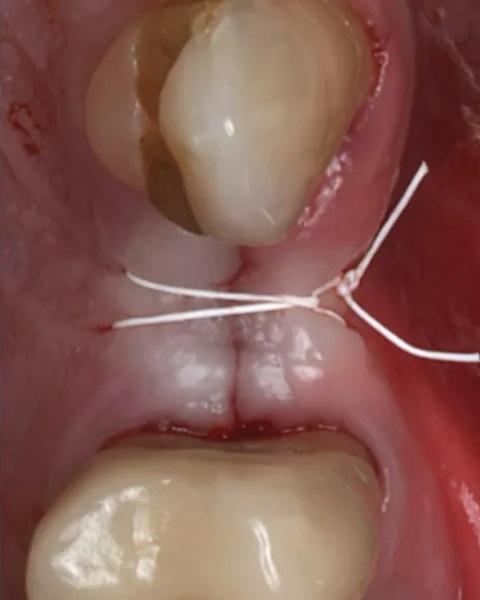

Фото 9. Пробка из ксеногенно-аллопластического биоматериала помещена в лунку, и наложен матрацный шов из ПТФЭ.